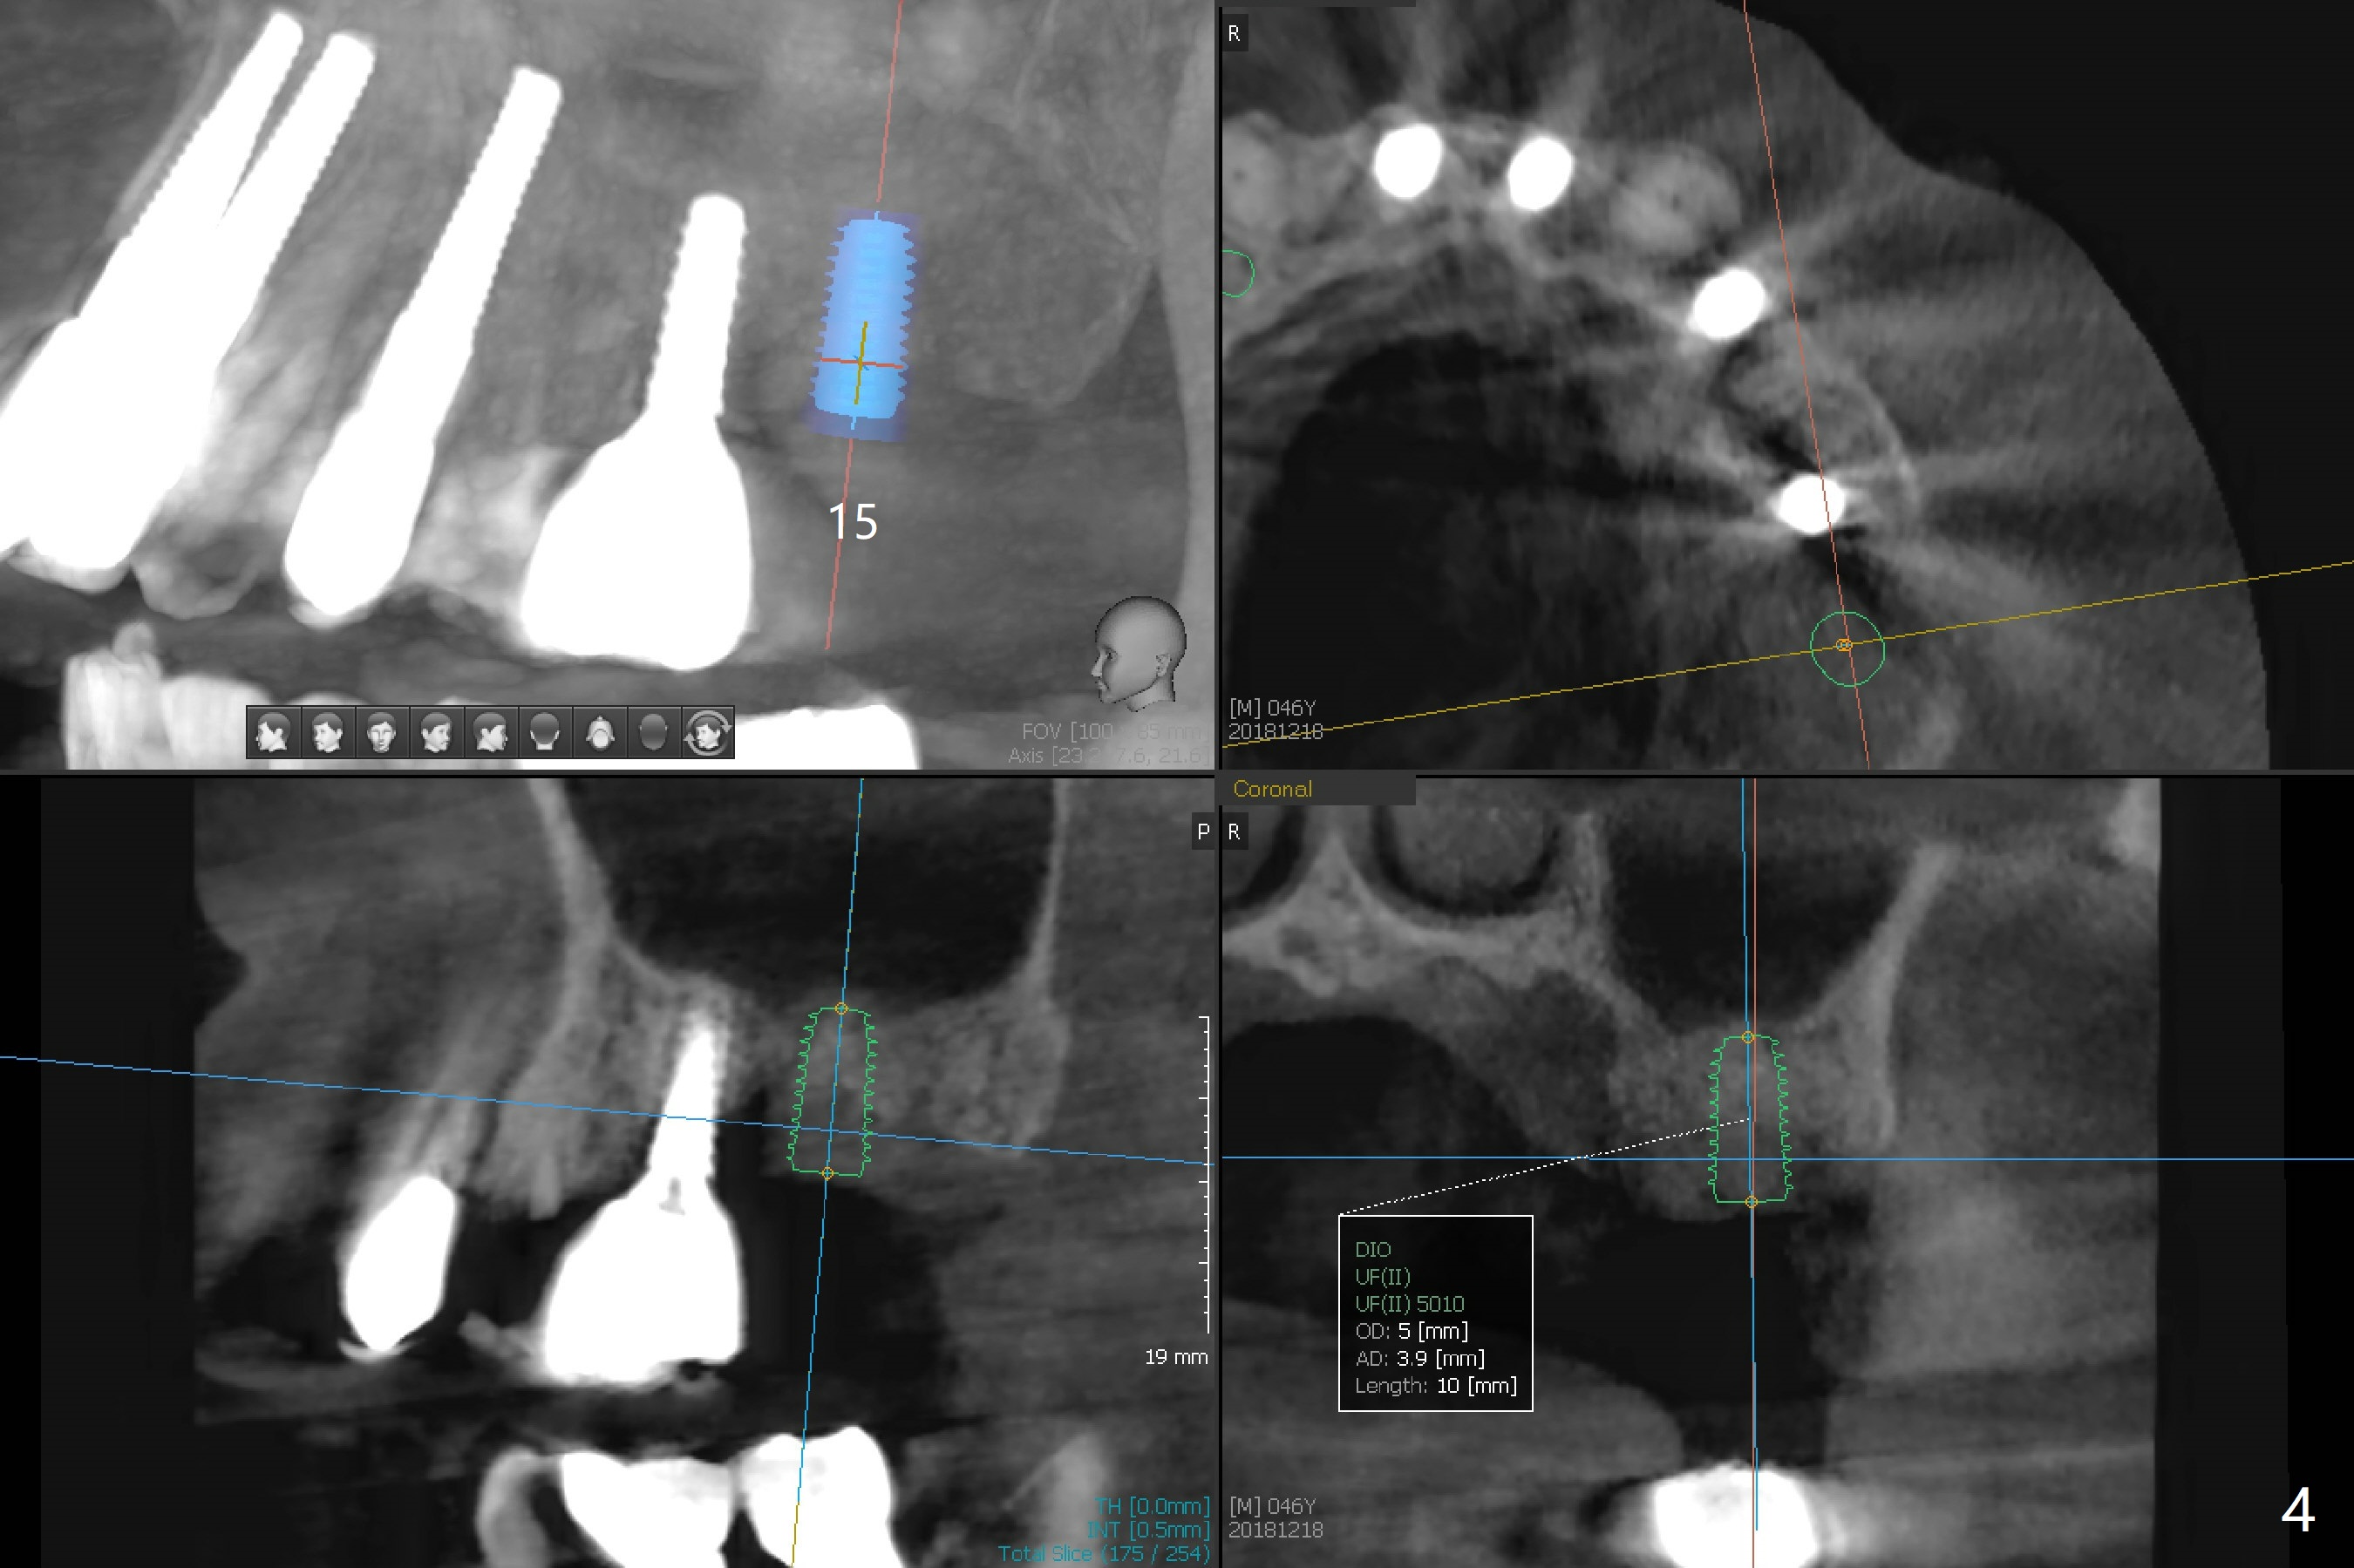

A 46-year-old man requests immediate implants at #4 and 5 because of pain associated with advanced periodontitis. Implants at #15 and 29 were removed with bone graft 4 months earlier (Fig.1). All of the 4 implants will be placed with guide. When 3.5 mm implants are placed at #4 and 5, they appear to be too close to each other (Fig.2). It is alright when the diameter changes to 3.0 mm (Fig.3). While a 5x10 mm implant will be placed at the 2nd stage (Fig.4), a 4x11.5 mm one will be placed in the same appointment as #4 and 5 (Fig.5).